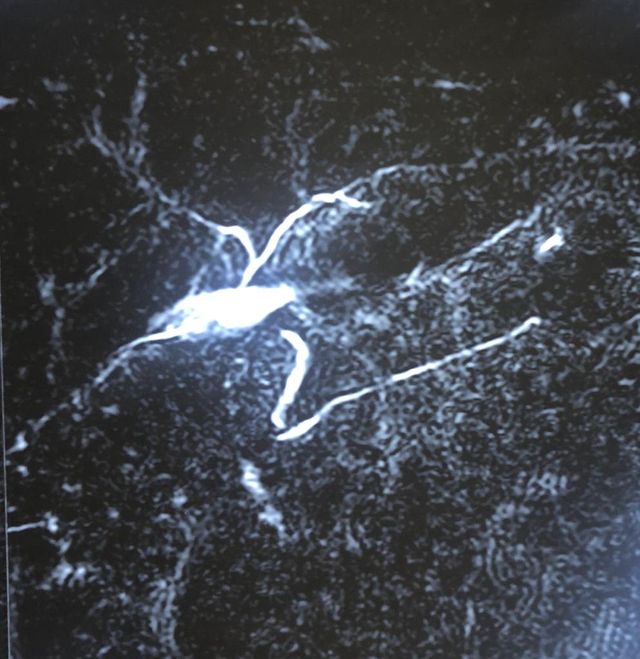

Challenging emergency during the COVID: Child’s A CLD with HUGE gastric varices uncontrolled

Child’s A CLD with HUGE gastric varices uncontrolled by Endoscopic glue and attempted EUS coiling. One salvage option would be TIPSS with balloon vascular occlusion but due to logistics we went for modified sugiura procedure. Splenectomy + Gastro esophageal devascularisation with anterior Gastrotomy and overseeing of gastric varices with pyloroplasty. Images show 1 CECT showing large gastric fundal varices. 2,3,4 Gastro Esophageal devasc 5, 6 Large fundal varices before and after oversewing. 7. Anterior gastrotomy 8. Pyloroplasty. Postoperative recovery was uneventful.